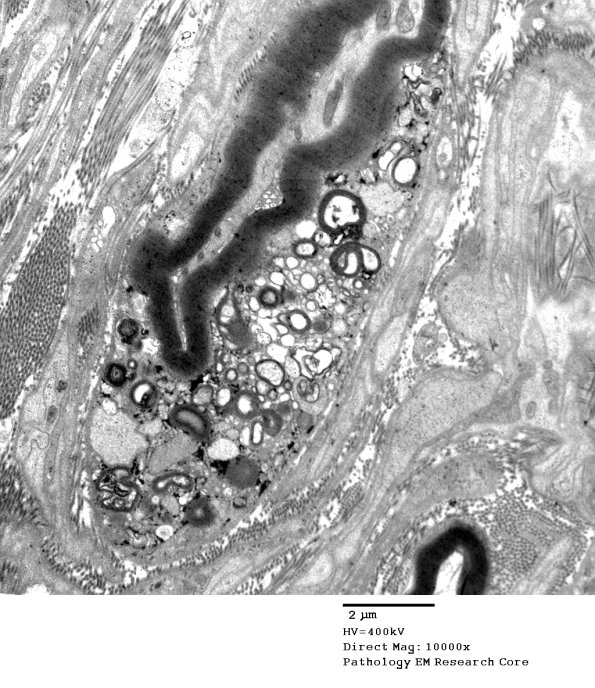

A macrophage with engulfed myelin adjacent to a partially myelinated axon which is itself intact. (electron micrograph)